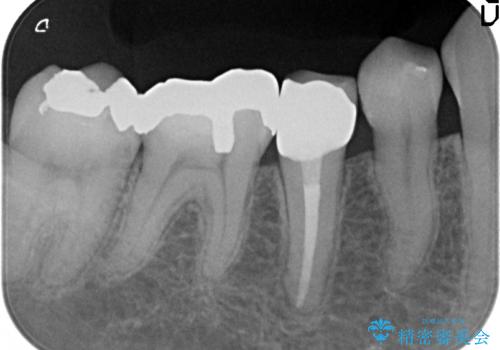

- 右下の歯でものを咬むと違和感があるので診て欲しいといらっしゃった方の症例です。

右下5番目の歯に根尖病変を認めたため、再根管治療を行い、オールセラミッククラウンによる補綴を行いました。